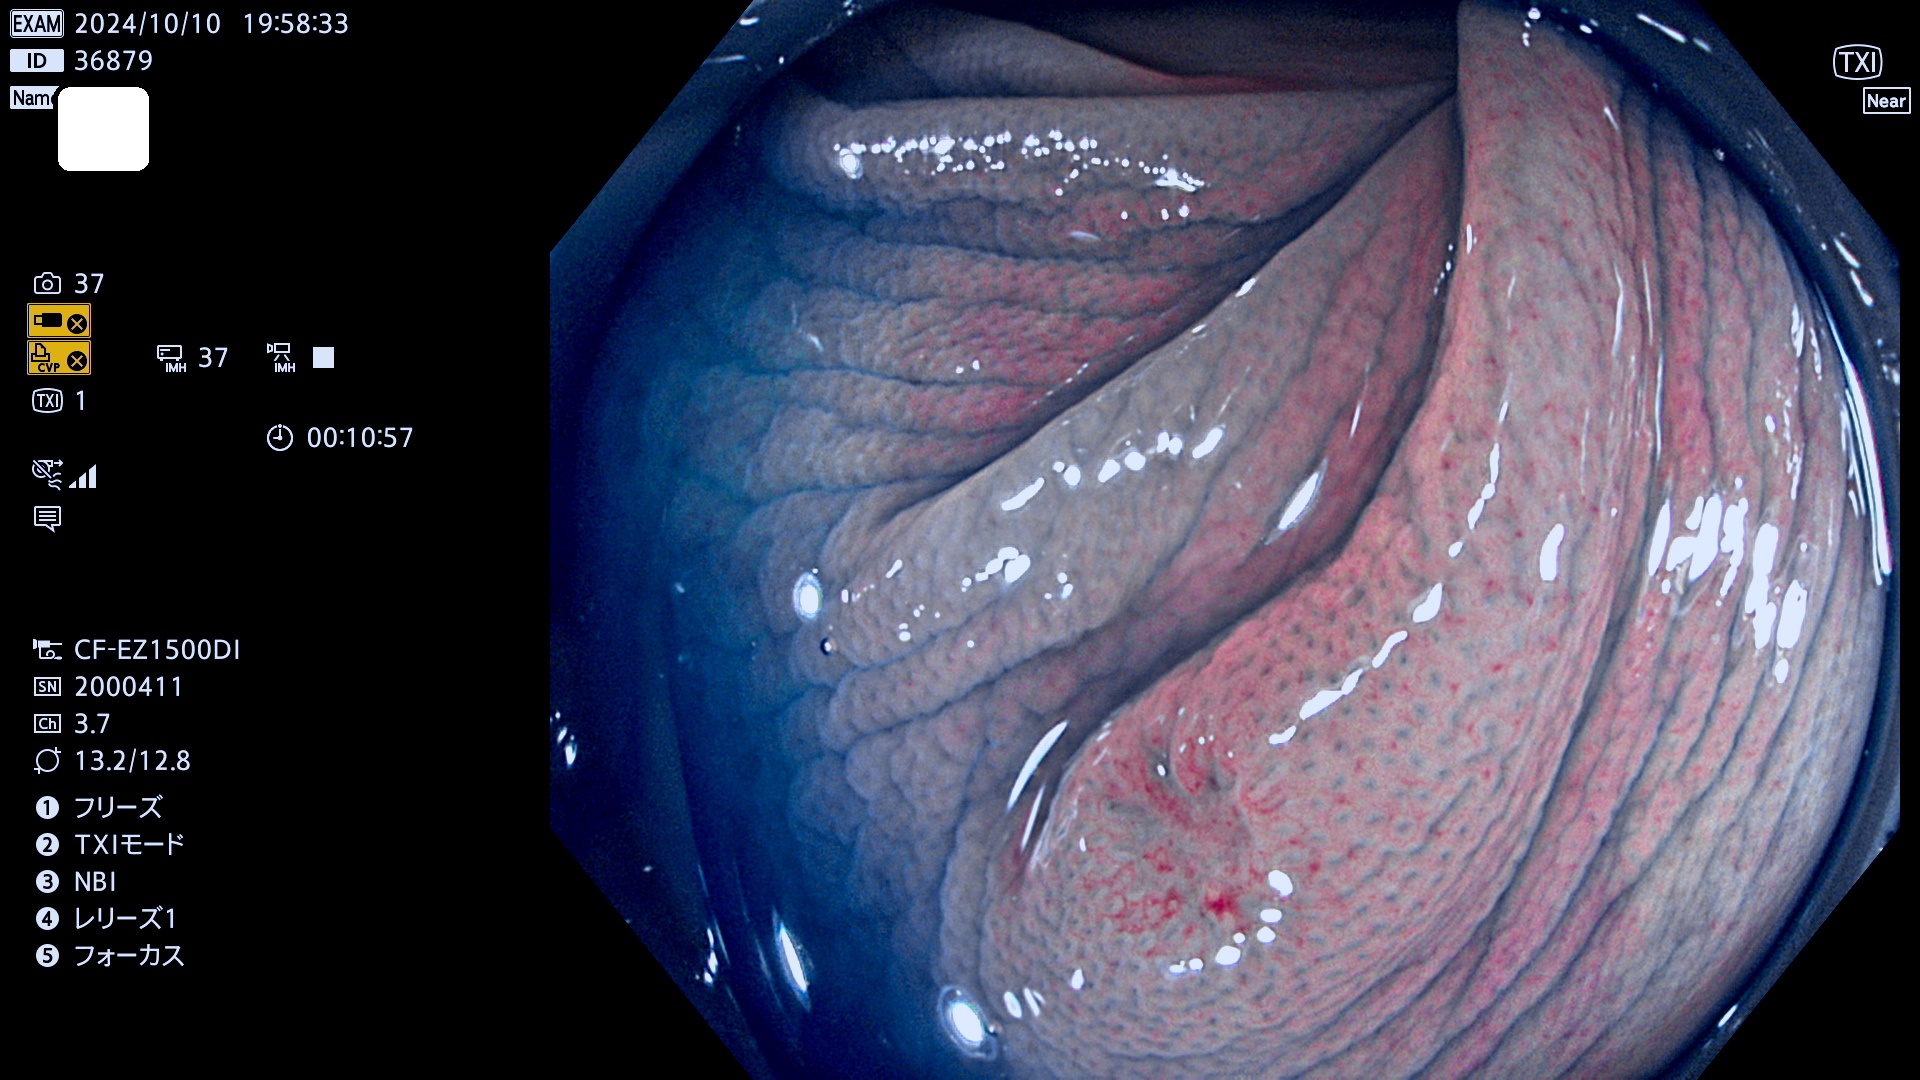

今週のUb、Uc型腺腫

完全に平坦な物をUb、陥凹している物をUcと呼びます。最も発見が難しく危険な病変です。

毎週の検査(木・金・土・日)に発見されたUb、Uc型・腺腫を、その週の日曜の夜にUPし1週間、提示します。

抽出の対象期間 2024年10月10日〜10月13日の4日間(48件の検査)7件 (7/48=14%)